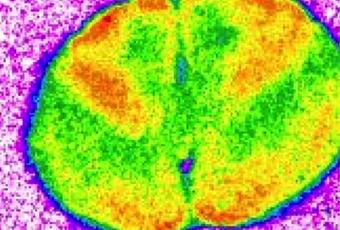

- l'imagerie cérébrale montre également que le médicament altère la fonction de zones cérébrales clés impliquées dans l'apprentissage et la mémoire ;

- de plus, l'exposition à long terme au médicament nuit à la capacité de ces zones cérébrales impliquées dans l'apprentissage et la mémoire à communiquer entre elles (cf visuel).

Source: J Neurochem August, 2018 doi: 10.1111/jnc.14549 Chronic, intermittent treatment with a cannabinoid receptor agonist impairs recognition memory and brain network functional connectivity (Visuel Francisco Mouro, iMM/FMUL)